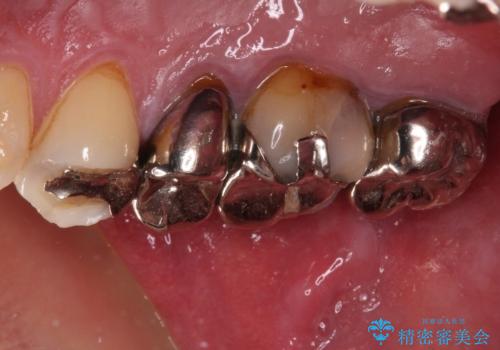

- ものが挟まるとのことで来院された患者様です。

一度は治療せずに放置していましたが、1年後のメインテナンスの際に悪化していることが分かったことから、補綴治療を行うこととしました。

神経を抜いてある歯はむし歯が進行しても痛みを感じることがないため、気がついたときには著しくむし歯が進行している可能性があります。

早めの対応とすることで、抜歯を回避できることはもちろん、外科処置などの本来必要のない処置を行わずに対処することができました。